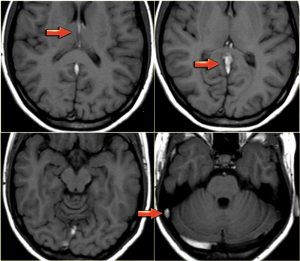

Mất dòng chảy tín hiệu trống (flow void) bình thường trên MRI (Absence of normal flow void on MRI)

Trên hình ảnh xung spin-echo, tĩnh mạch não thông thoáng (patent cerebral veins) thường sẽ biểu hiện tín hiệu thấp do flow void. Flow void (tín hiệu trống do dòng chảy) được thấy rõ nhất trên xung T2W và FLAIR, nhưng đôi khi cũng có thể thấy trên xung T1W.

Huyết khối sẽ biểu hiện dưới dạng mất dòng chảy tín hiệu trống (flow void). Mặc dù đây không phải là dấu hiệu hoàn toàn đáng tin cậy, nhưng nó thường là một trong những điều đầu tiên giúp chúng ta nghĩ đến khả năng có huyết khối tĩnh mạch. Bước tiếp theo phải là chụp MRI có tiêm thuốc tương phản.

Hình bên trái: Trên xung T2W với dòng chảy tín hiệu trống (flow void) bình thường trong xoang sigma và tĩnh mạch cảnh trong bên phải (mũi tên màu xanh). Hình bên phải: xoang sigma và tĩnh mạch cảnh trong bên trái có tín hiệu cao bất thường do huyết khối (mũi tên màu đỏ).

Hình. Mất dòng chảy tín hiệu trống (flow void) bình thường trên MRI.

Các hình ảnh cho thấy tín hiệu cao bất thường trên xung T1W do huyết khối. Huyết khối kéo dài từ các tĩnh mạch não sâu (deep cerebral veins) và xoang thẳng (straight sinus) đến xoang ngang và xoang sigma bên phải. Ghi nhận dòng chảy tín hiệu trống (flow void) bình thường ở xoang ngang bên trái trên hình ảnh dưới cùng bên phải.

Mất dòng chảy tín hiệu trống (flow void) bình thường trên MRI có thể rất hữu ích trong việc phát hiện huyết khối tĩnh mạch, nhưng có một số cạm bẫy (pitfalls) mà chúng ta sẽ thảo luận sau. Dòng chảy chậm (Slow flow) có thể xảy ra trong tĩnh mạch và gây ra tăng tín hiệu trên xung T1W.